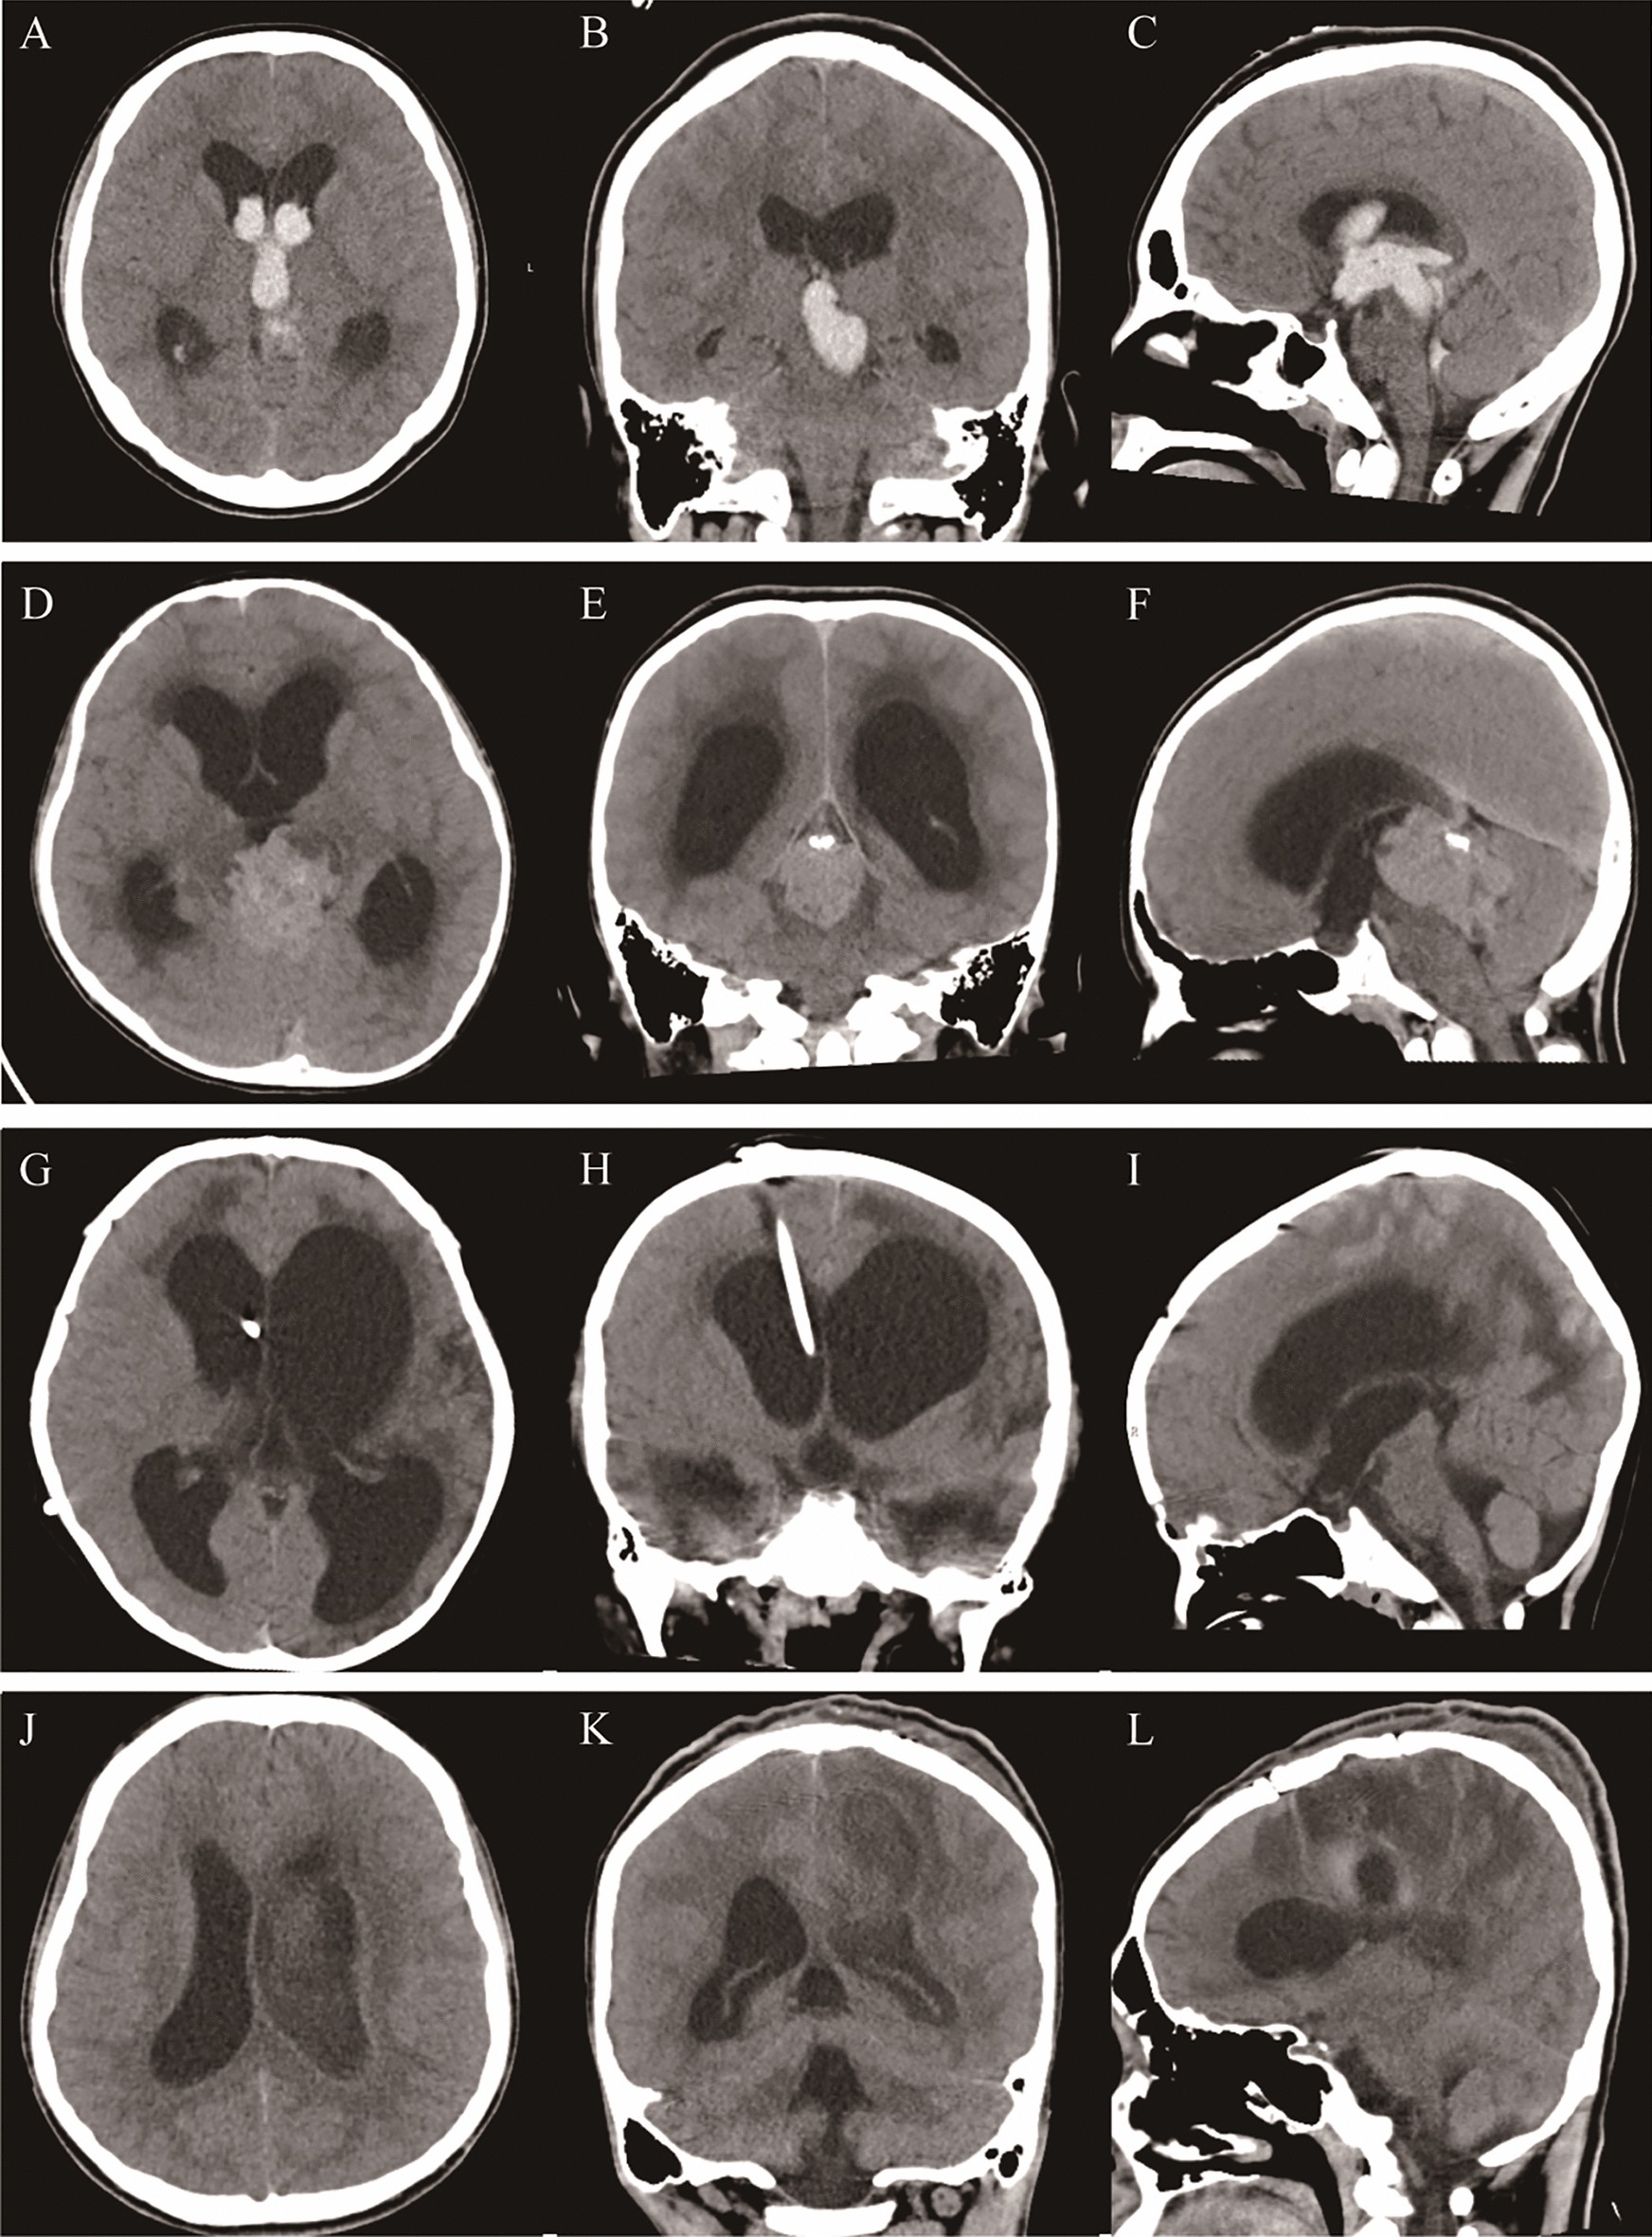

Figure 2

From: Modified ventriculoperitoneal shunt applied to temporary external ventricular drainage

CT imaging features of various acquired hydrocephalus. Imaging of secondary hydrocephalus due to intraventricular hemorrhage: Axial (A), coronal (B), and sagittal (C), Imaging of obstructive hydrocephalus caused by brain tumor: Axial (D), coronal (E), and sagittal (F), Imaging of secondary intracranial infection after ventriculoperitoneal shunt: Axial (G), coronal (H), and sagittal (I), Imaging of brain abscess with intracranial infection: Axial (J), coronal (K), and sagittal (L).